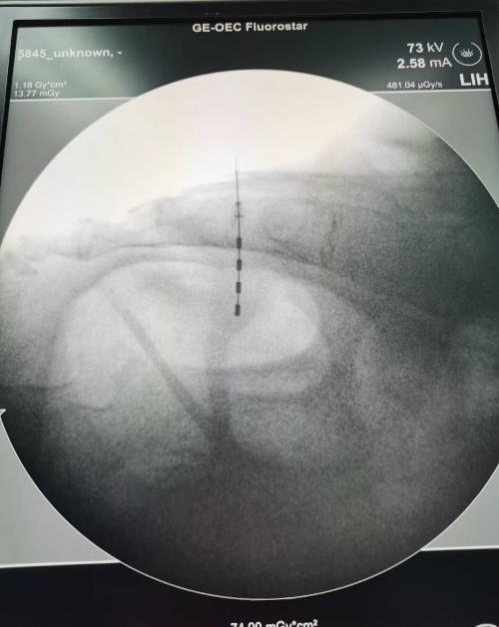

2024年3月29日带领团队顺利为患者实施了一期治疗——骶神经刺激电极植入术,电极植入左侧骶3神经孔,电极植入位置精准,术中反复测试,患者应答反应良好,手术十分顺利。

电极植入位置精准